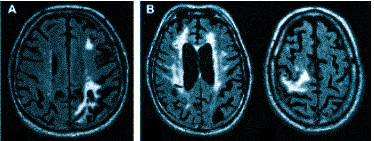

Множественные ишемические очаги при сосудистой деменции на МРТ: отсутствие памяти на недавние события и неадекватное поведение не являются признаками старости, своевременная диагностика деменции и патогенетическая терапия помогут замедлить прогрессирование болезни

Очень часто при МРТ головного мозга, особенно, в пожилом возрасте встречаются признаки «дисциркуляторной энцефалопатии». Этот термин и клинический, и диагностический. Он отражает «старение» мозга в условиях недостаточности общей кровообращения. Совсем необязательно, что у таких пациентов обнаружатся бывшие инсульты, хотя мелкие («лакунарные») все же иногда встречаются. Дисциркуляторная энцефалопатия проявляется при МРТ в виде единичных или множественных мелких очагов лейкоарайоза (термин предложен в 70-е годы для обозначения мелких участков глиоза, то есть распада белого вещества мозга), той или иной степени атрофии, часто гидроцефалии. Гидроцефалия может быть с лейкомаляцией – изменениями белого вещества мозга вокруг желудочков, отражающее его распад, нарушение ликврообращения и замену нормального вещества мозга глиозной тканью (своего рода «рубцом»).

демиелинизацию при рассеянном склерозе и иных атрофических процессах;

Что покажет МРТ головы с контрастом

После контрастирования при МРТ детализация мелких структур значительно выше. Магнитно-резонансную томографию с усилением предпочитают онкологи, так как можно увидеть контуры опухоли, определить степень ее инвазии (прорастание в близлежащие ткани), диагностировать метастазы. МРТ с введением контраста лучше показывает изменения после операции, патологические очаги в головном мозге на фоне рассеянного склероза, при болезни Альцгеймера. Чаще используют препараты на основе хелатов гадолиния. Мировая практика подтверждает высокий профиль безопасности: при грамотном применении осложнения встречаются крайне редко.